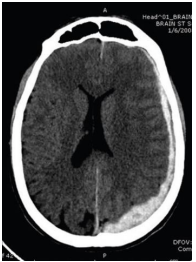

Internet: Advanced Trauma Life Support. Tenth Edition. Copyright© 2018 American College of Surgeons 633 N. Saint Clair Street Chicago, IL 60611-3211.

Paciente vítima de traumatismo cranioencefálico, após avaliação primária e secundária, realiza um exame de imagem. No que diz respeito ao caso hipotético e à interpretação do exame de imagem, assinale a alternativa que apresenta a hipótese diagnóstica correta.